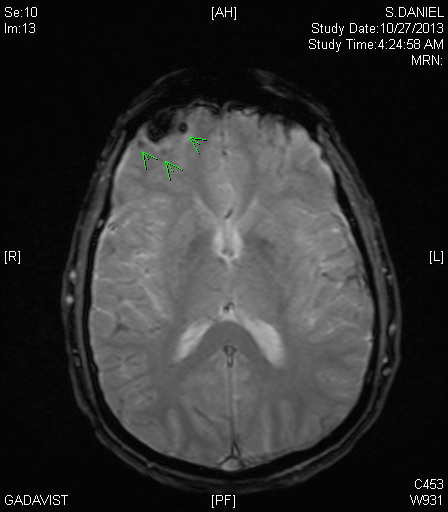

By that time, I had also had an MRI to further clarify the situation. When I later viewed the MRI, I was stunned to see what I call the “money shot.” This is an image (or images) that contain the key findings, usually marked up by the radiologists. Here was mine (note green arrows at top left, which on CT and MRI imaging represents the right frontal area, which may be better seen if you click on the image to view a larger version):

The interpretation was:

“Abnormality in the right frontal lobe with mild gliosis and enhancement and small amount of blood products. Findings could represent subacute infarction or contusion. Possibility of neoplasm is felt to be less likely but cannot be entirely excluded. Recommend followup imaging in four weeks to assess the temporal evolution of this lesion.”

Viewing this after my hospitalization, I was in denial that this could be me. How could this terrible looking image be my brain? Cancer? Stroke? I’ve seen many brain images, including many that were much worse than this. But these were of patients, not me. This can’t be me!